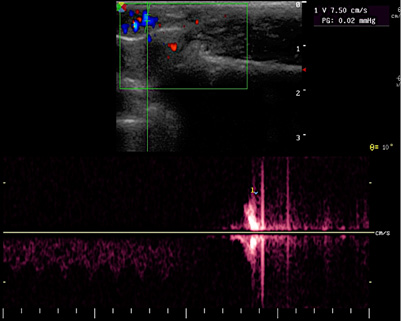

Спустя 14 суток от создания модели у всех животных групп 2 и 3 визуализированы семенные вены (до 1,8 мм, р > 0,05 между группами) и зарегистрирован рефлюкс (рис. 3A, 3B). Средний диаметр семенных вен (до 2,1 мм) был зарегистрирован на 30-е сутки.

Рисунок 3. Эхограмма (А) и допплерограмма (В) на 30-е сутки. При мануальной компрессии брюшной полости определён рефлюкс по семенным венам кролика со скоростью 7,5 см/с

Figure 3. Echogram (A) and Doppler image (B) on day 30. During manual compression of the abdomen, reflux in the rabbit’s spermatic veins was detected with a flow velocity of 7.5 cm/s